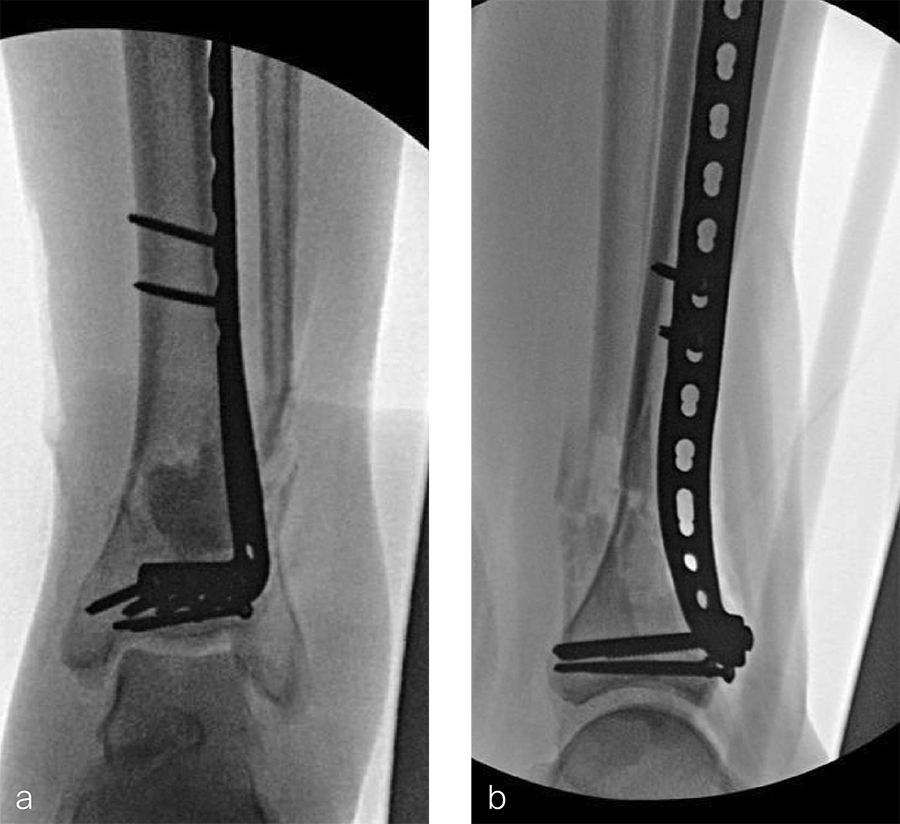

Two months later, the patient had a staged cement spacer removal and hardware removal followed by a new spacer placement (Fig 4). When microbiological cultures were negative for 5 days he was taken to the OR for definitive fixation and bone grafting. RIA bone graft from the ipsilateral femur was taken, a new anterior lateral plate was placed with an adjunct IM nail (and angle stable screws) as the distal plafond was now one articular block (Fig 5).

The patient has been followed up monthly for more than 5 months and has shown continued consolidation of the bone defect (Fig 6). Furthermore, he is weight bearing as tolerated without significant pain. The leg lengths are equal and the range of motion at the ankle is 10/25 dorsiflexion/plantarflexion. He has mild pain over the ankle joint but no pain at the fracture site.